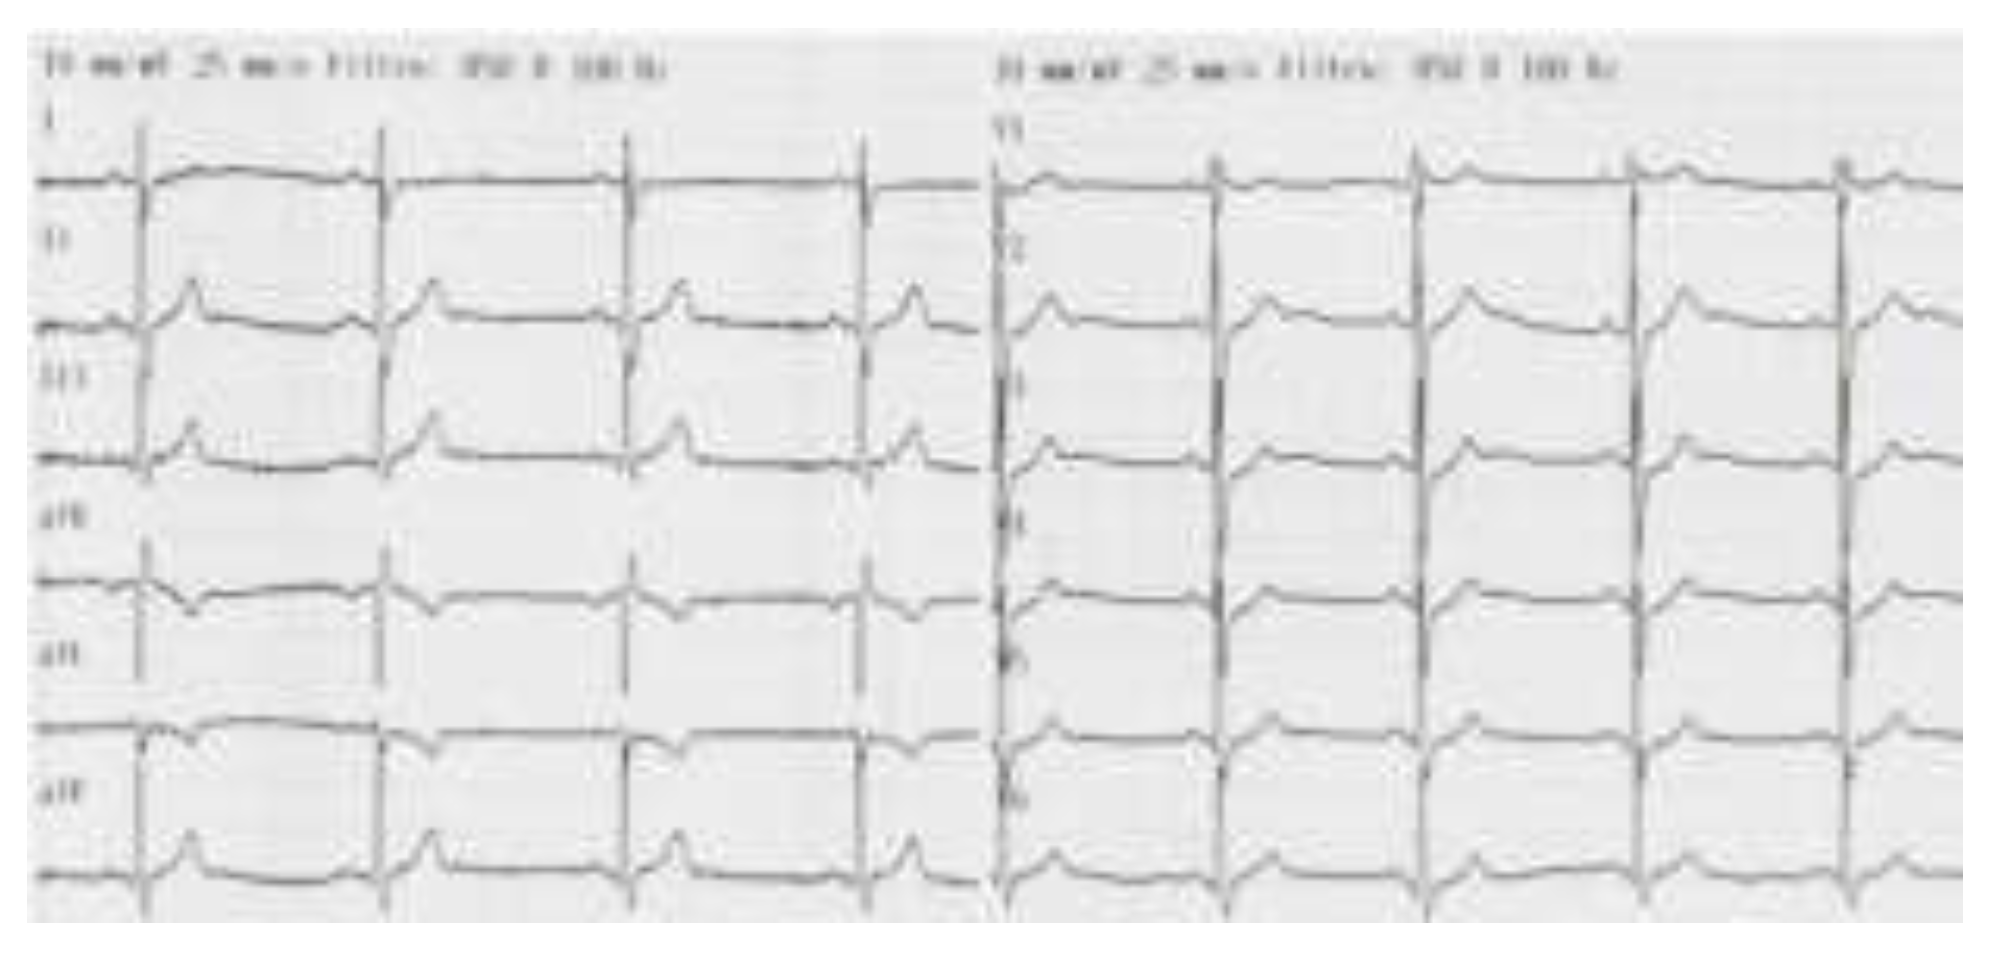

- Non-ST segment elevation myocardial infarction.

- Incomplete right bundle branch block.